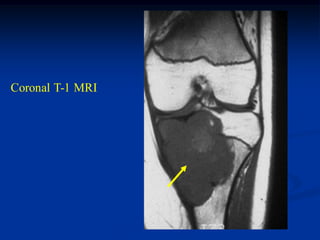

11 year male with

ABC distal femur

Lateral view

Coronal T-1 MRI

Axial T-1 MRI

Axial T-2 MRI

18 months later

without treatment